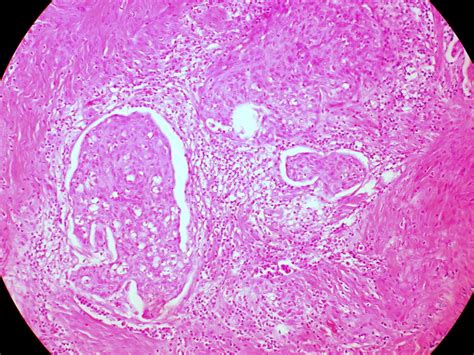

Alright, so what exactly determines how aggressive an SCC cancer is? Several key elements come into play. First off, where the SCC originates plays a big role. SCC of the skin, for instance, tends to be less aggressive than SCC found in the lungs or esophagus. That’s because the skin has a different environment and access to the lymphatic system, which can influence how and where the cancer spreads. Then there’s the size and depth of the tumor . Bigger tumors or those that have grown deeper into the tissue are often more aggressive. These tumors have a greater chance of spreading to nearby lymph nodes or distant parts of the body. Also, the differentiation grade of the cancer cells matters. This refers to how much the cancer cells look like normal cells. Well-differentiated SCC cells resemble normal cells more closely, and tend to be less aggressive. Poorly differentiated cells, which look very different from normal cells, are often more aggressive and likely to spread. Patient health and overall immune system strength can have an impact too. A stronger immune system might be able to slow down the cancer’s progression, while a weakened immune system could allow it to grow more rapidly. And of course, treatment factors also come into play; early detection and prompt treatment can significantly improve outcomes and reduce the chances of aggressive behavior. Let’s not forget about the specific subtype of SCC. Different subtypes, such as those caused by HPV (Human Papillomavirus), may behave differently. HPV-related SCCs sometimes show unique characteristics. Understanding these factors helps doctors assess the SCC’s likely aggressiveness and plan the best course of action. It’s all about tailoring the approach to what each individual patient needs.